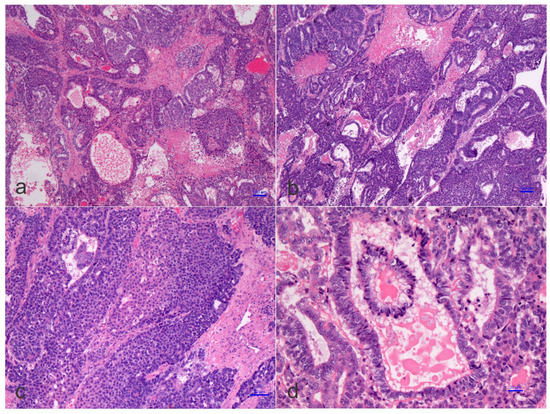

1.3. Pathological Features